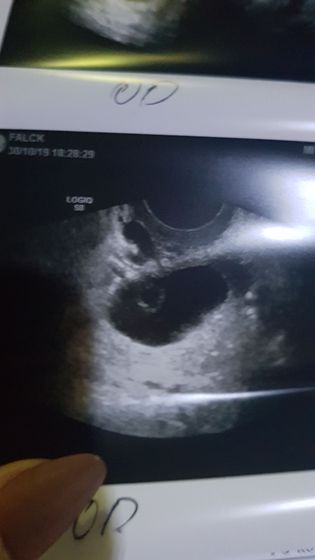

Девочки, у кого была киста желтого тела? Подскажите каких размеров и на какой день цикла? И посмотрите на фото пожалуйста, она у вас выглядела так? Ну или похожа хотя бы? Мне просто не могут определить что это за образование, уже 2 врачей прошла, 3 узистов и все плечами пожимают, говоря что это какая то жидкость в жидкости и только один узист предположил что это может быть киста желтого тела. Я уже себе места не нахожу, успокаивпет одно, что все говорят что это доброкачественное образование, но якобы очень необычное ?

На 12 день цикла был простр темный шарик на яичнике, сказали фолликулярная киста, на 14 день пошла еще раз ( посмотреть что не растёт), а в нутри этой кисты выросло нечто ? у меня была однв внематочная уже в трубе, вот теперь боюсь внематочной в яичнике?

Вот 12 день цикла

Так это матка же) а у меня в яичнике это образование